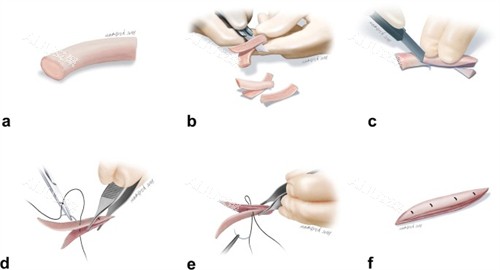

杨万忠医生凭借二十多年的执业生涯和对鼻整形技术的深入研究,在业内树立了良好的口碑。他擅长多种鼻整形技术,尤其是肋骨鼻等自体软骨隆鼻手术,能够根据个人的脸型和形象设计出适合的鼻形方案。现在,想要预约杨万忠医生进行鼻整形的朋友可以通过公众号、线上平台或电话轻松预约,开启您的美丽之旅。